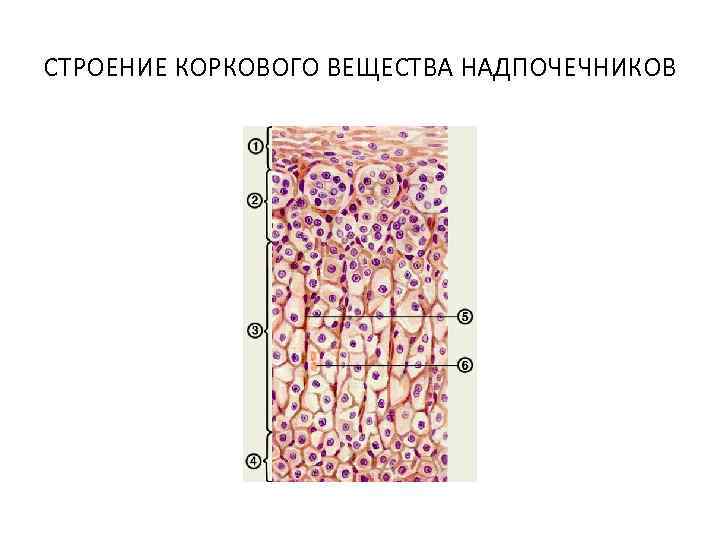

СТРОЕНИЕ КОРКОВОГО ВЕЩЕСТВА НАДПОЧЕЧНИКОВ

СТРОЕНИЕ КОРКОВОГО ВЕЩЕСТВА НАДПОЧЕЧНИКОВ